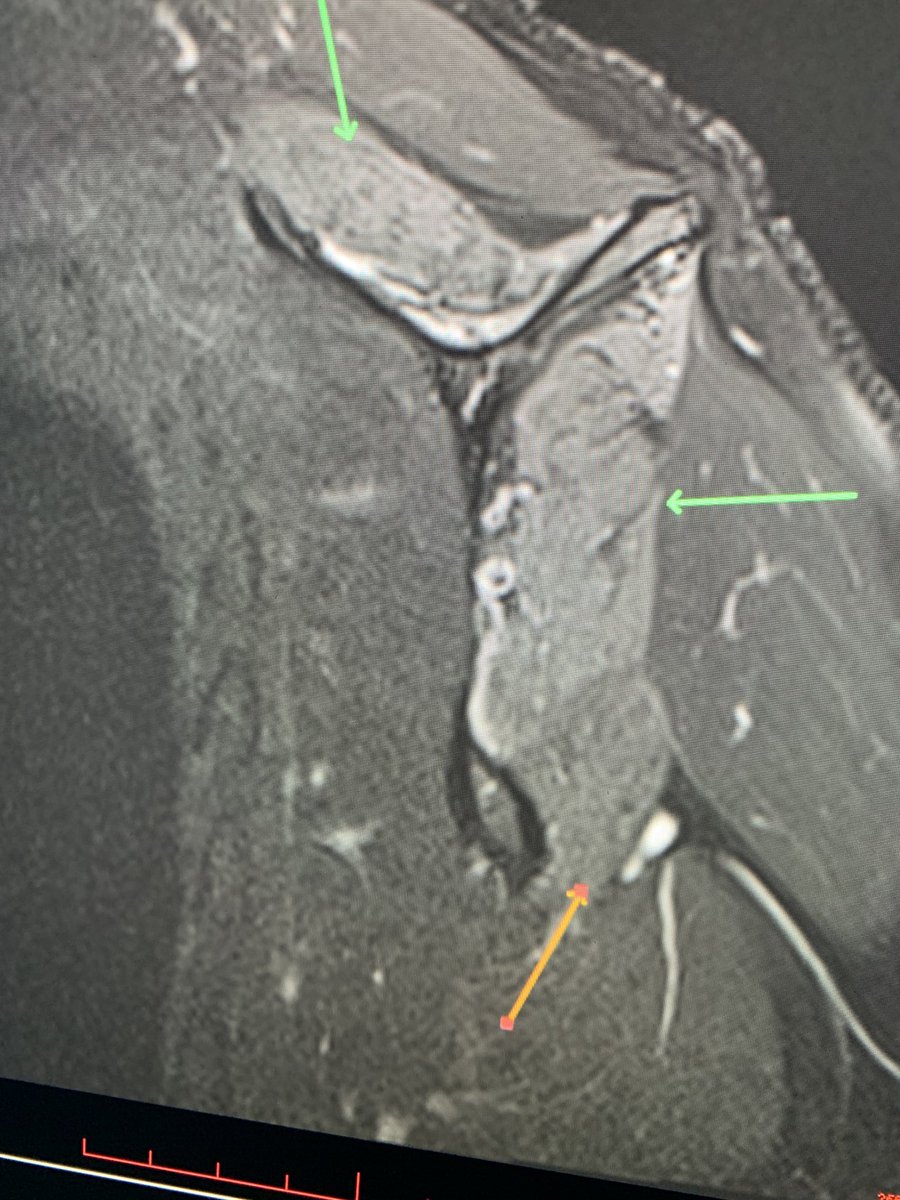

Young RHD pt in MVC with R shoulder dislocation and large cuff avulsion. Also w/ a DENSE brachial plexopathy with no motor or sensation below the deltoid. Axillary n. is ok. Everything distal to that is out. Plexus MRI shows edema w intact plexus Haven’t seen this in a bit